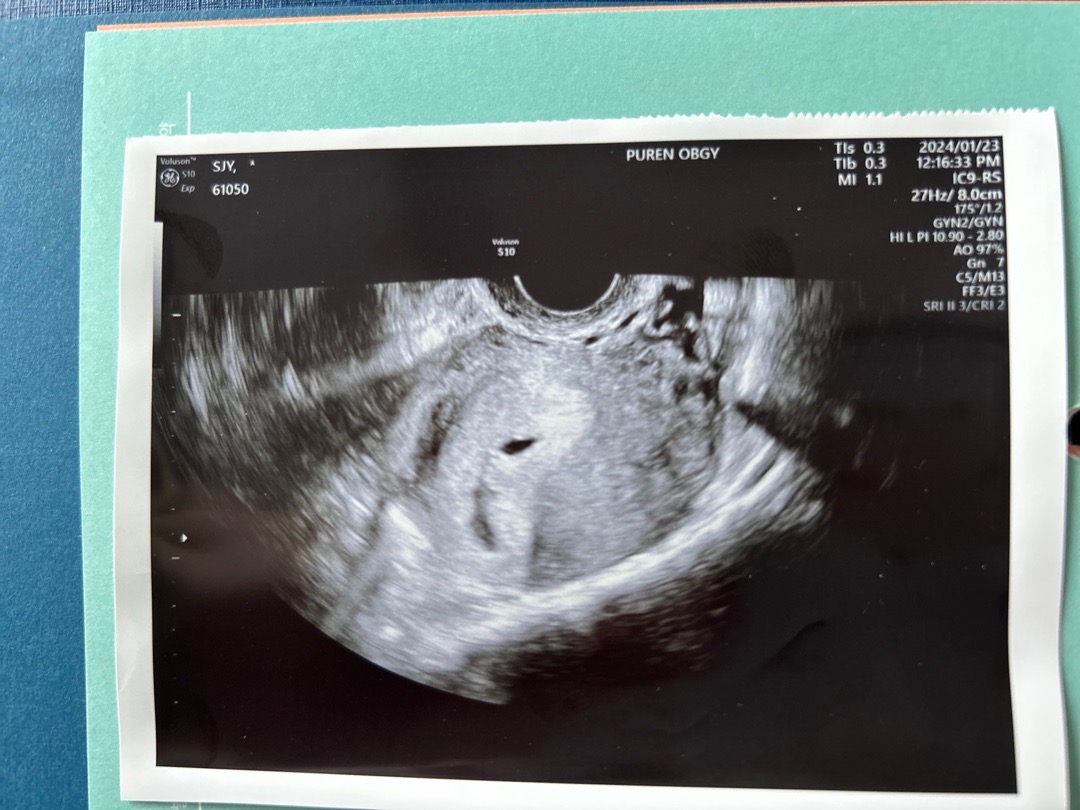

너무 긴장해서 질문을 많이 못하고 왔어요ㅠㅠ 아기집이 8cm가 맞나요? 어느 부분을 봐야할지 모르겠어요ㅠㅠ

4주 5일 0.45 cm 였어요 이후 하루에 1mm씩 커진다고 하셨어요

사이즈를 따로 초음파시에 측정한 게 아닌거 같아요! 5주차에 보통 일센치 정도같아요

전 5주차에 1cm였어요! 4주3일에는 0.58이였구요!